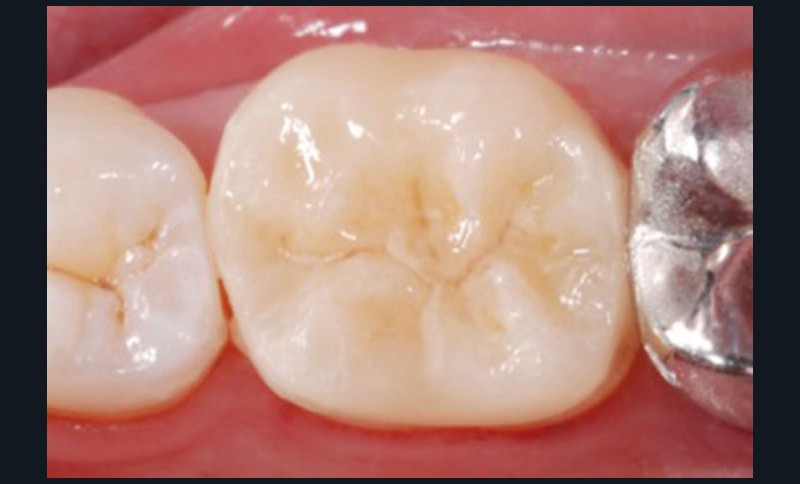

Restaurer sans tenon la dent dépulpée (fig. 4, 5, 6)

Selon les analyses de la littérature récente, la dent dépulpée n’est pas plus fragile que la dent pulpée. En revanche, les pertes de structure (a fortiori mésio-occluso-distale, lorsque les deux crêtes marginales sont perdues), et plus encore les tenons radiculaires, sont les éléments qui fragilisent la dent dépulpée. Ainsi, aussi souvent que possible, la dent dépulpée sera reconstituée sans tenon.

Lorsque la dent présente 4 parois résiduelles, une restauration en composite direct est indiquée. Pour 3 parois avec au moins une crête marginale, une restauration directe ou indirecte convient, si toutefois elles sont collées, car le collage augmente la résistance mécanique de l’organe dentaire résiduel. Pour 2 parois sans crêtes marginales, l’épaisseur des parois et la nature de la dent (les prémolaires étant plus fragiles que les molaires) vont permettre d’arbitrer entre reconstitution partielle collée ou endocouronne : le sertissage de la dent résiduelle ainsi obtenu la renforce considérablement. Le recours au tenon radiculaire sera donc réservé aux situations de délabrement très important, et il sera utilisé dans un but de rétention, et non pas dans un but de consolidation de l’organe dentaire.